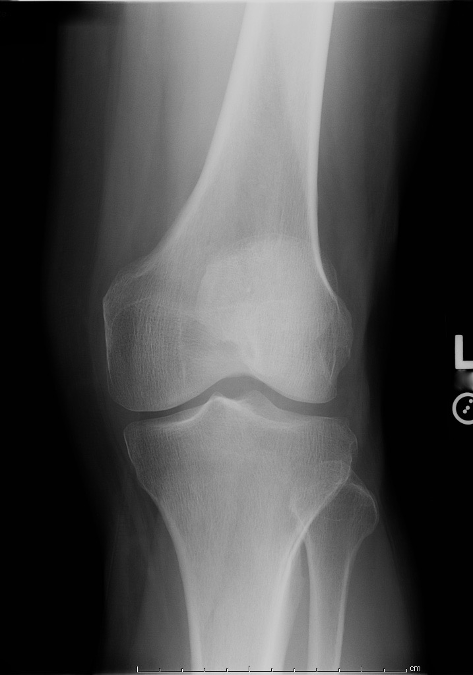

Identify the structure labeled 1 in the AP projection of the knee shown in Figure 2–16.

A Lateral condyle B Lateral epicondyle C Medial condyle D Medial epicondyle

Medial epicondyle

Which of the following statements regarding the radiograph in Figure A is (are) true?

1. The tibial eminences are well visualized.

2. The intercondyloid fossa is demonstrated between the femoral condyles.

3. The femorotibial articulation is well demonstrated.

1 and 3 only

Which of the following is (are) accurate positioning or evaluation criteria for an AP projection of the normal knee?

- Femorotibial interspaces equal bilaterally.

- Patella superimposed on distal tibia.

- CR enters ½ in. distal to base of patella.

1 only